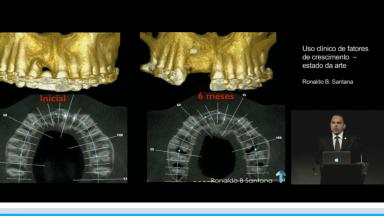

Uso clínico de fatores de crescimento – estado da arte

A apresentação expõe de forma crítica o estado atual da utilização clínica dos fatores de crescimento, trazendo uma discussão sobre a eficácia das diferentes técnicas, a possibilidade de otimização dos resultados clínicos, formas de simplificar o procedimento e o prognóstico de longo prazo.

A literatura será revisada e ilustrada com casos clínicos utilizando os fatores de crescimento clinicamente disponíveis no mercado para construir um conceito sobre o tema discutido e auxiliar na tomada de decisão.